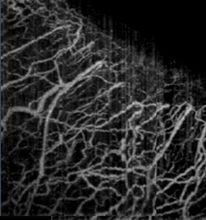

普通OCT技術可以實現組織內部微觀形態結構的三維活體成像,通過與Doppler技術、光譜技術、偏振技術等結合,可以獲得三維空間分辨的生物組織生理功能信息。特別是,通過將OCT與動態散射技術結合可以實現無標記三維微血管造影,獲得組織內部血流灌注的三維活體成像。

光學相干層析成像圖5. 人眼角鞏膜緣處微血管造影[2]